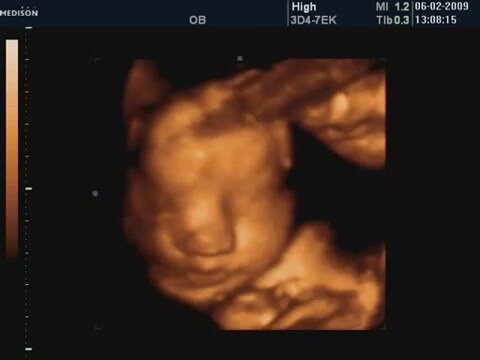

31 Haftalık Bebeğin 4 Boyutlu Ultrason Görüntüsü